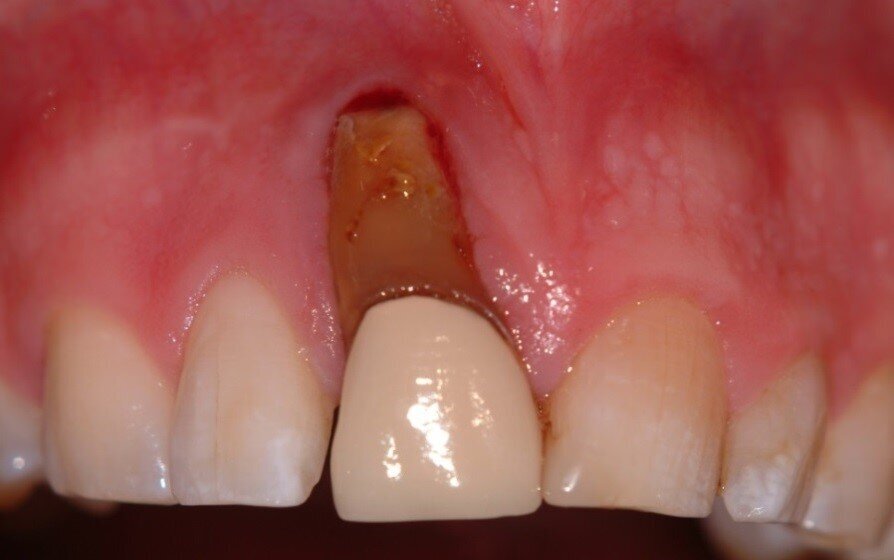

2. Extraction and the split root confirmed (Fig. 4)